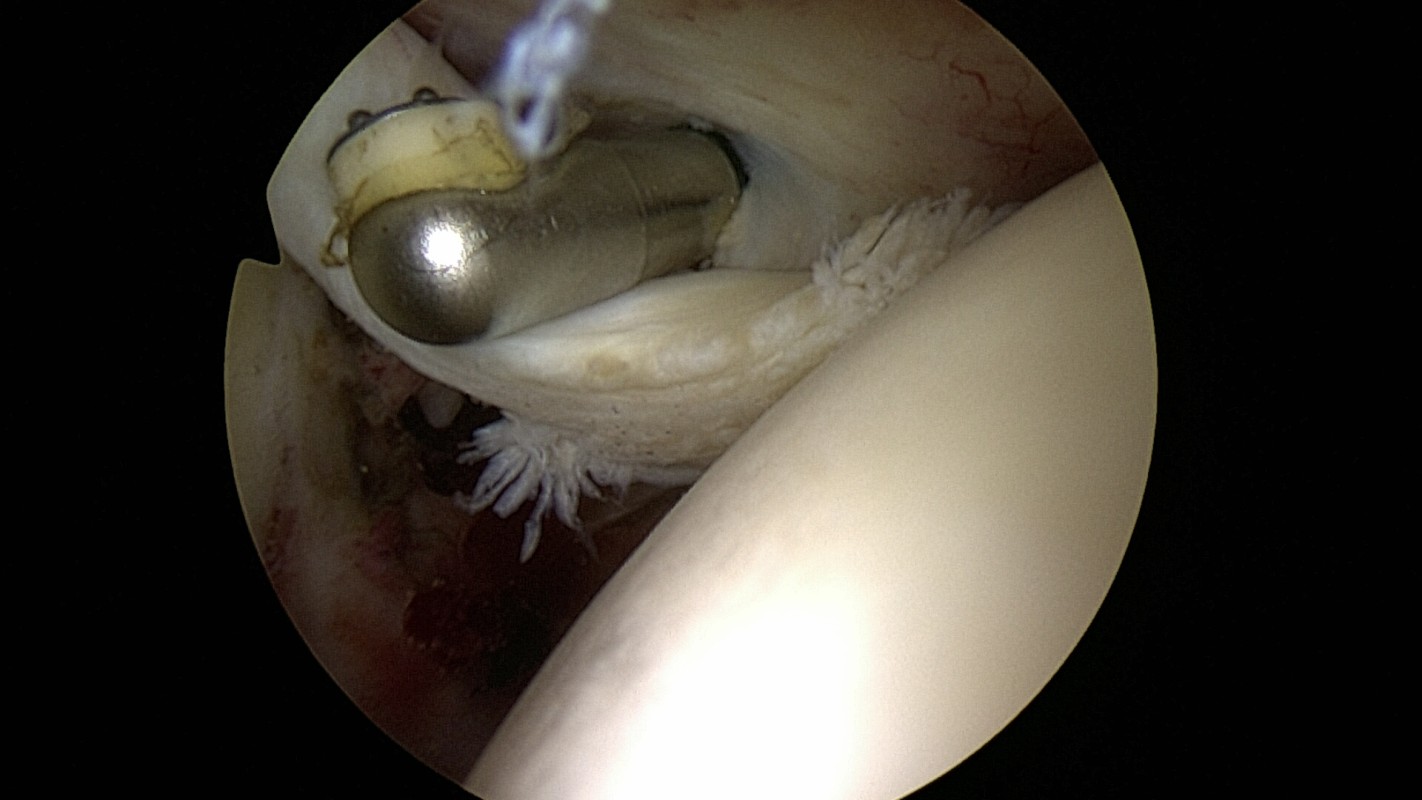

• Ténodèse : on effectue une réparation de ce tendon qui est alors fixé sur la tête de l’humérus, par exemple par une vis.

Exemple de réparation du LBi (=Ténodèse) par une vis